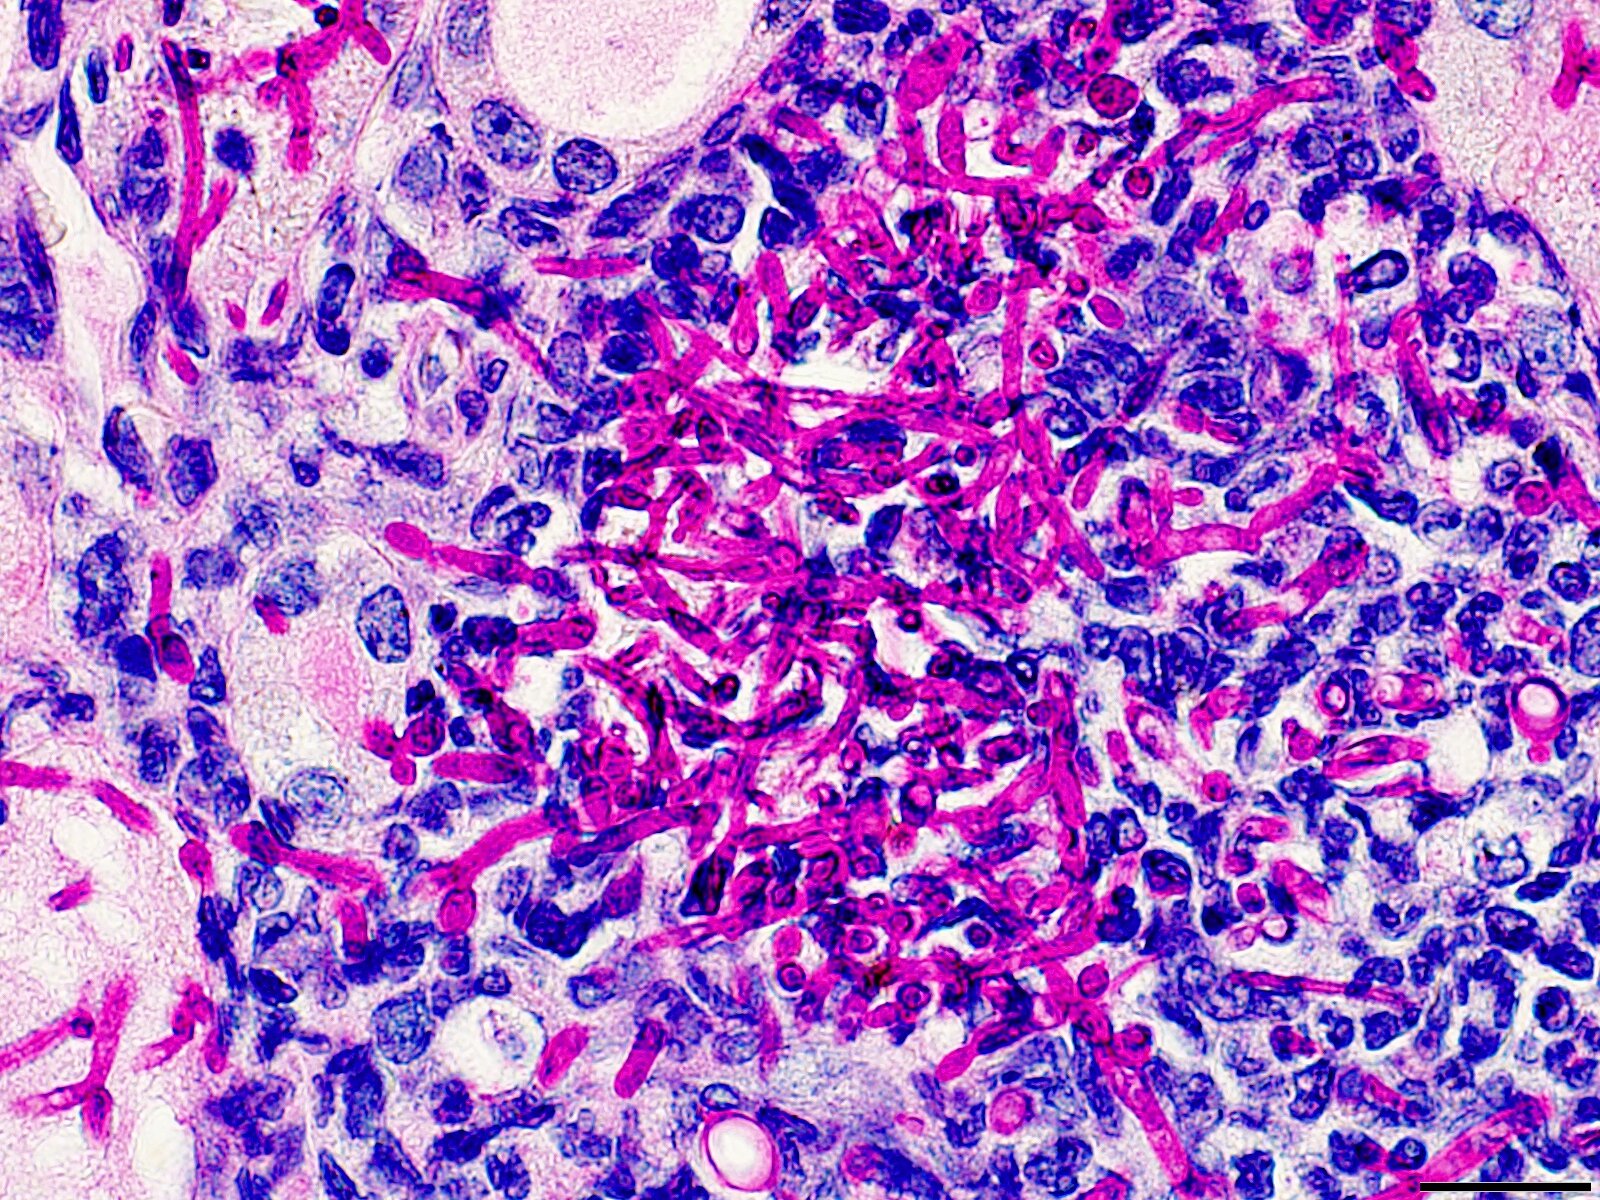

Studija objavljena u travanjskom izdanju Cell Host & Microbe otkrila je metabolički put koji bi mogao promijeniti pristup liječenju sistemske kandidijaze – opasne gljivične infekcije koja se sve teže liječi zbog otpornosti na antifungalne lijekove. Umjesto razvoja novih antimikotika, istraživači predlažu imunološko metaboličko reprogramiranje, konkretno aktivaciju enzima PYGL (glikogen fosforilaza, jetreni oblik) u neutrofilima, bijelim krvnim stanicama ključnima za obranu od Candida albicans.

Tim pod vodstvom Partha Biswasa, profesora mikrobiologije na Sveučilištu Stony Brook, pokazao je da neutrofili u modelu kandidijaze na miševima nadoknađuju nedostatak glukoze upravo aktivacijom PYGL-a. Ovaj enzim omogućava stanicama da koriste skladištene rezervne ugljikohidrate, čime poboljšavaju svoju antifungalnu funkciju. Ključna je činjenica da je beta-2 adrenergički agonist – lijek već odobren za ljudsku uporabu u drugim indikacijama – u eksperimentu pojačao obranu domaćina od infekcije.

Otkriće metaboličkog puta u neutrofilima nudi alternativu tradicionalnom liječenju gljivičnih infekcija